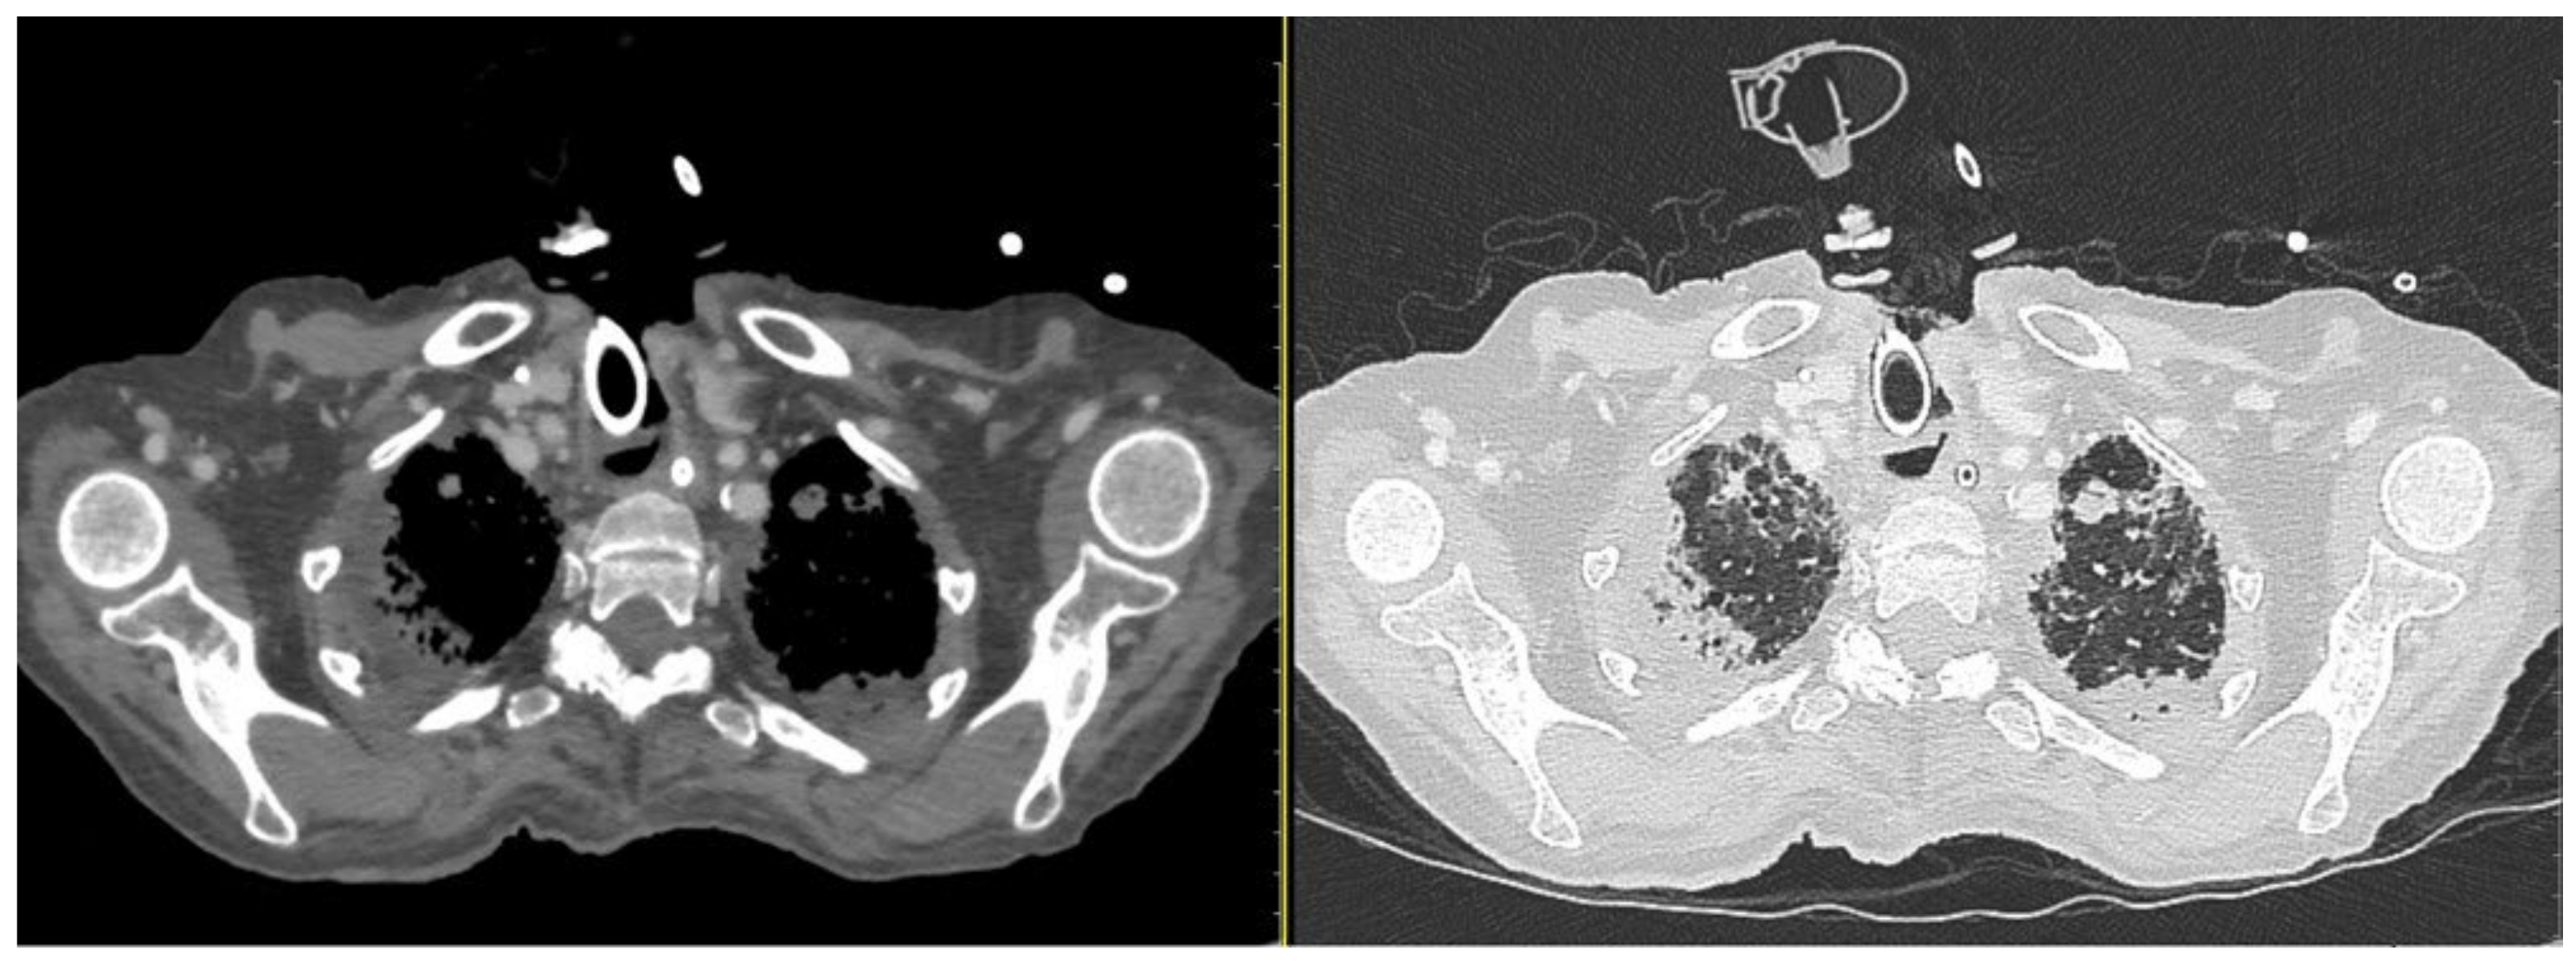

Figure 3.

CT scan windows showing metastasis and inflammatory phenomena on both sides of the lung. (On the left, axial parenchymal lung section. On the right, axial lung window). During hospitalization, bacterial pneumonia began, worsened by secondary viral (Cytomegalovirus) and fungal pneumonia. The patient received a triple antibiotics course with an antiviral, an antifungal, and systemic and local inhalational corticosteroids. However, despite the medical therapy, the chest condition deteriorated progressively (Figure 4).